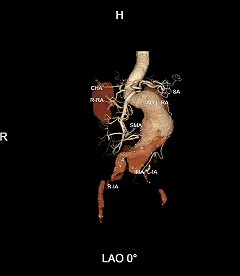

现病史:患者8幼时前无显著诱因下出现头晕伴恶心呕吐,呕吐物为胃内容物,忽视物旋转,无呕血黑便,无胸闷气促,无胸痛,遂至本地医院就诊查。CTA提醒自动脉瘤,腹自动脉多发钙化,胸自动脉多发钙化斑块。

? 术前影像学资料

IV型胸腹自动脉瘤,瘤颈和双侧髂动脉严沉扭曲,瘤体巨大,内脏分支血管开吵嘴度倾斜